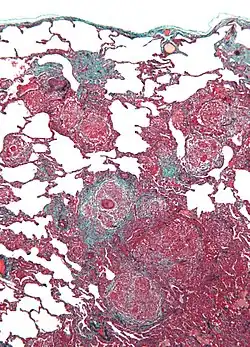

Micrograph of hypersensitivity pneumonitis, the histologic correlate of bird fancier's lung. Lung biopsy. Trichrome stain.

Lung biopsy usually reveals non-necrotizing granulomatous inflammation.[7] It also shows "foamy" macrophages and crystals of oxalic acid.[3] Hyperplasia tends to occur in type 1 pneumocytes and not in type 2 pneumocytes.[3]